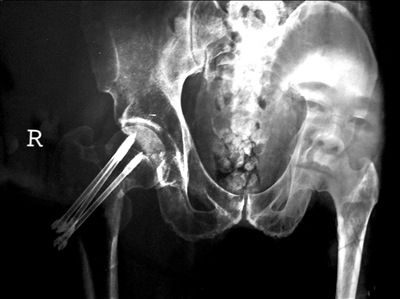

车祸导致罗先生右股骨颈骨折。他在北京协和医院西院接受手术治疗后,腿疼加剧,提前回院复查。结果发现,手术中打入骨骼中的加压螺钉脱落,骨折固定位置错位。罗先生不得不再次手术,并在患处打入新的螺钉。

2008年10月29日晚6点左右,现年56岁的罗先生骑车至西单附近时发生车祸,被就近送到协和医院西院(北京协和医院西院前身是北京邮电医院,在合并入协和医院后,成为北京协和医院西院区,是三级甲等医院,协和医院很多大夫在东西两院都有出诊)。经检查,罗先生被确诊为右股骨颈骨折。次日凌晨3点,医院创伤骨科的张医生为罗先生做了闭合内固定手术。

记者看到,手术记录中的手术步骤栏写有“扩孔、攻丝后拧入ICOS空心螺钉”,这样的螺钉共打入3枚,透视见“骨折复位,固定良好”,手术过程顺利。

在家人的陪同下,罗先生提前到医院复查。X光片显示,骨折处用于固定的加压螺钉脱落,骨折固定位置错位。

经过多方协调后,罗先生于2009年1月5日在北京另外一家三级甲等医院进行修复手术治疗,将脱落的3枚螺钉取出,又重新打入3枚螺钉。但由于最佳治疗时机已被贻误,且骨折处已经打过3枚螺钉,打入新螺钉时没有合适位置,导致罗先生至今无法正常走路,只能坐在轮椅上依靠一位亲戚的“贴身”照顾度日。

司法鉴定机构于今年4月19日出具的鉴定结论显示,手术效果不佳的原因,和手术中三枚空心钉进针不足,固定力不够坚强有关。

鉴定机构认为,医院选择的治疗方法是正确的,不过,手术过程中虽然有C臂机监控,但三枚空心钉内固定的受力范围难以保证绝对均匀,术后X光片显示三枚空心钉进针不足,针尖距离股骨头皮质面偏远,导致其固定力下降,影响了骨折的正常愈合。因此,认定“手术过程中骨折复位欠佳、固定力不够坚强,存在缺点”,并作出结论:

医院方存在“固定不充分、复位不完全”的医疗过失,这与罗先生的修复手术后果之间存在少部分因果关系,其理论参与度为25%。